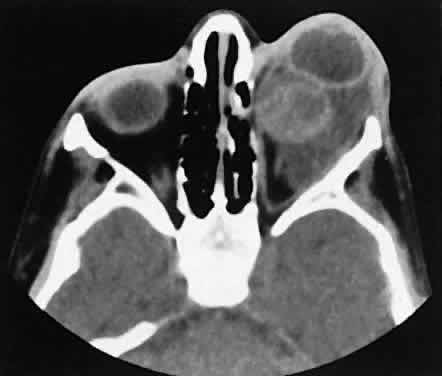

Nonspecific inflammatory dacryoadenitis shows enlargement of the lacrimal gland, which typically molds to the shape of the globe (Fig. 6). The adjacent bone is normal, and contrast enhancement of the gland usually is fairly homogeneous. Bilateral involvement may be apparent with certain conditions such as Sjogren's syndrome, sarcoidosis, lymphoma, or even Graves' orbitopathy, although enlarged EOM in the latter condition might make this a more obvious diagnosis.

Fig. 6. Nonspecific inflammatory dacryoadenitis. An isodense enlargement of the lacrimal gland is noted on axial (A) and coronal (B) views. Note the similarity to Figure 18.

Lymphomatous involvement of the lacrimal gland resembles inflammatory dacryoadenitis radiographically. The enlarged lacrimal gland conforms to the shape of the globe, and the adjacent bone is normal (Fig. 18). We are aware of three high-grade lymphomas that affected the orbit and lacrimal gland and indented the globe, but this is distinctly unusual. Non-Hodgkin's B-cell lymphomas represent the most common type of lymphoma to affect the orbit. Literally any structure in the orbit can be subject to lymphomatous involvement; therefore, a lymphoma should be suspected in the presence of any amorphous isointense infiltrative process.

Fig. 18. Axial (A) and coronal (B) views of lacrimal gland lymphoma. There is homogenous enhancement of the enlarged lacrimal gland. Compared with Fig. 6, there is no difference.